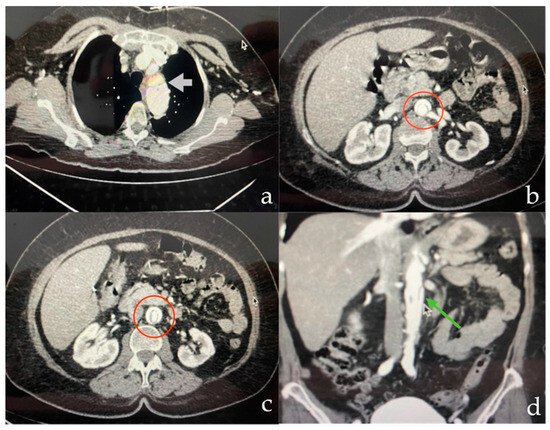

2. Detailed Case Description